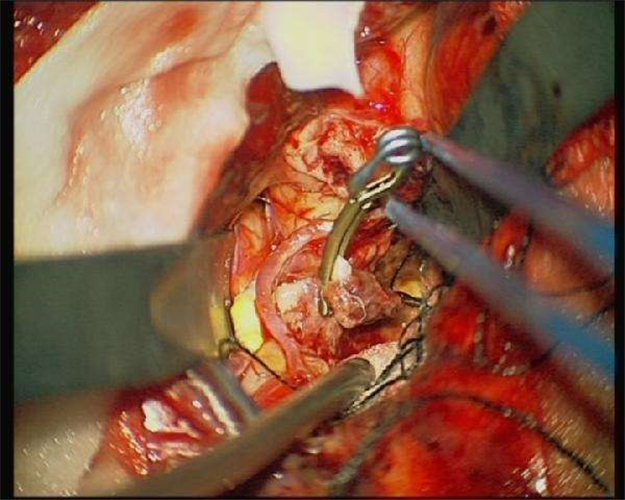

手術取出的腦血栓

手術摘除的腦血栓

手術治療腦血栓

腦血栓性動脈瘤治療